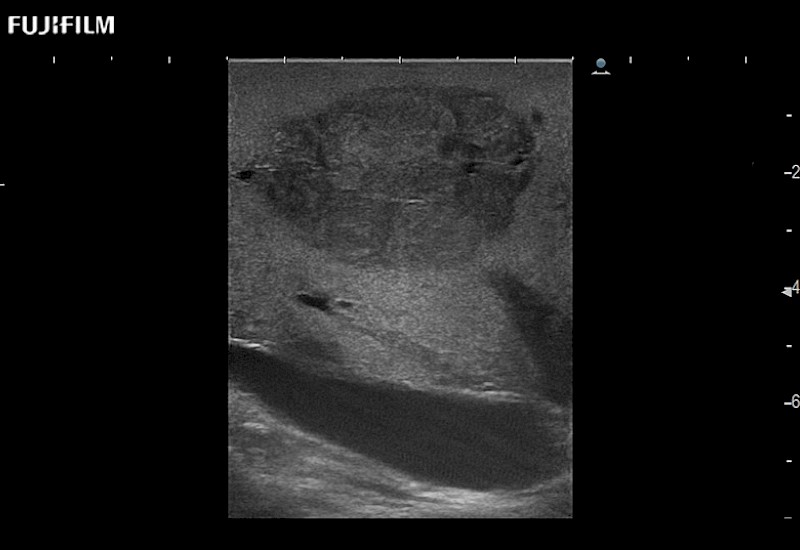

Our dedication to Surgical Oncology allows us to offer superior image quality, outstanding system reliability and intuitive use of cutting edge technology.